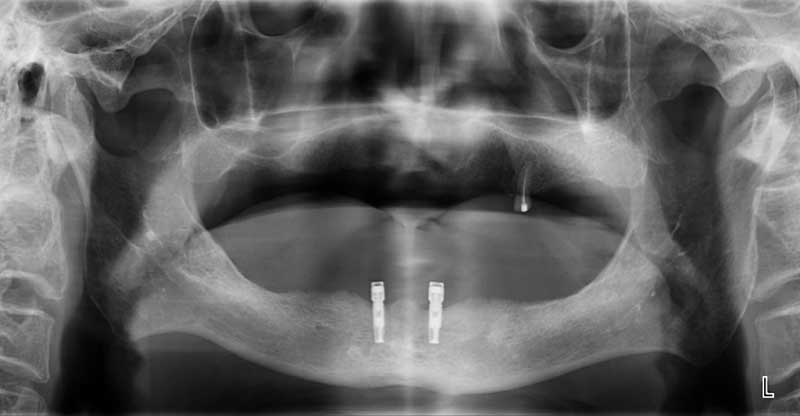

案例1